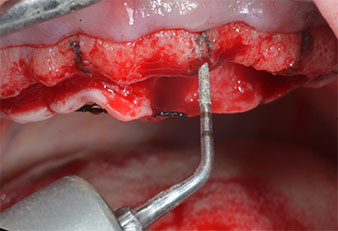

Uno strumento piezoelettrico (Piezomed I1) a forma di fiamma, rivestito in diamante, è stato usato per contrassegnare le posizioni dell'impianto e per eseguire una preparazione pilota (Fig. 3). Si è prestato attenzione a utilizzare un movimento verticale ascendente e discendente, con potenza ridotta, irrigazione completa e bassa pressione (inferiore a 300 g). Successivamente è stato applicato uno strumento pilota (Piezomed I2A/I2P) per l'ingrandimento iniziale delle sedi dell'impianto del diametro di 2 mm (Fig. 4), seguito da un inserto da 3 mm (Fig. 5).

In caso di osso denso, l'intera sequenza strumentale comprendente gli strumenti intermedi Piezomed Z25P e Z35P deve essere utilizzata per ampliare le osteotomie prima della successiva fase di allargamento.

Essi sono anche indicati per la preparazione vicino alla membrana del seno in relazione a procedure di rialzo interno o quando l'altezza ossea residua è inferiore a 4 mm.

Nel presente caso, gli strumenti Z25P e Z35P non sono stati utilizzati a causa dell'osso posteriore relativamente morbido, che è stato facilmente gestito mediante I3A/I3P.